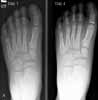

The next visit. Four days later,the child and his mother return to thepediatrician's office. The child now contradicts his earliercomplaint of a 1-day history of foot pain; instead, he reportsthat he has had left foot pain for about 2 weeks. Hisfoot has become markedly tender, red, and swollen duringthe past 24 hours (Figure 3). The previous night, the patient'stemperature was 38C (100.4F). He now walkswith a limp.

Figure 4 (A and B) shows the old and new x-rayfilms. Comparison of the lateral views reveals increasedsoft tissue swelling with a question of different soft tissuedensity along the periosteum of the metatarsal and cuneiformbones. There is no periosteal elevation. The roentgenographicchanges, coupled with the clinical picture,suggest a diagnosis of cellulitis or tenosynovitis. Osteomyelitisis a remote possibility.